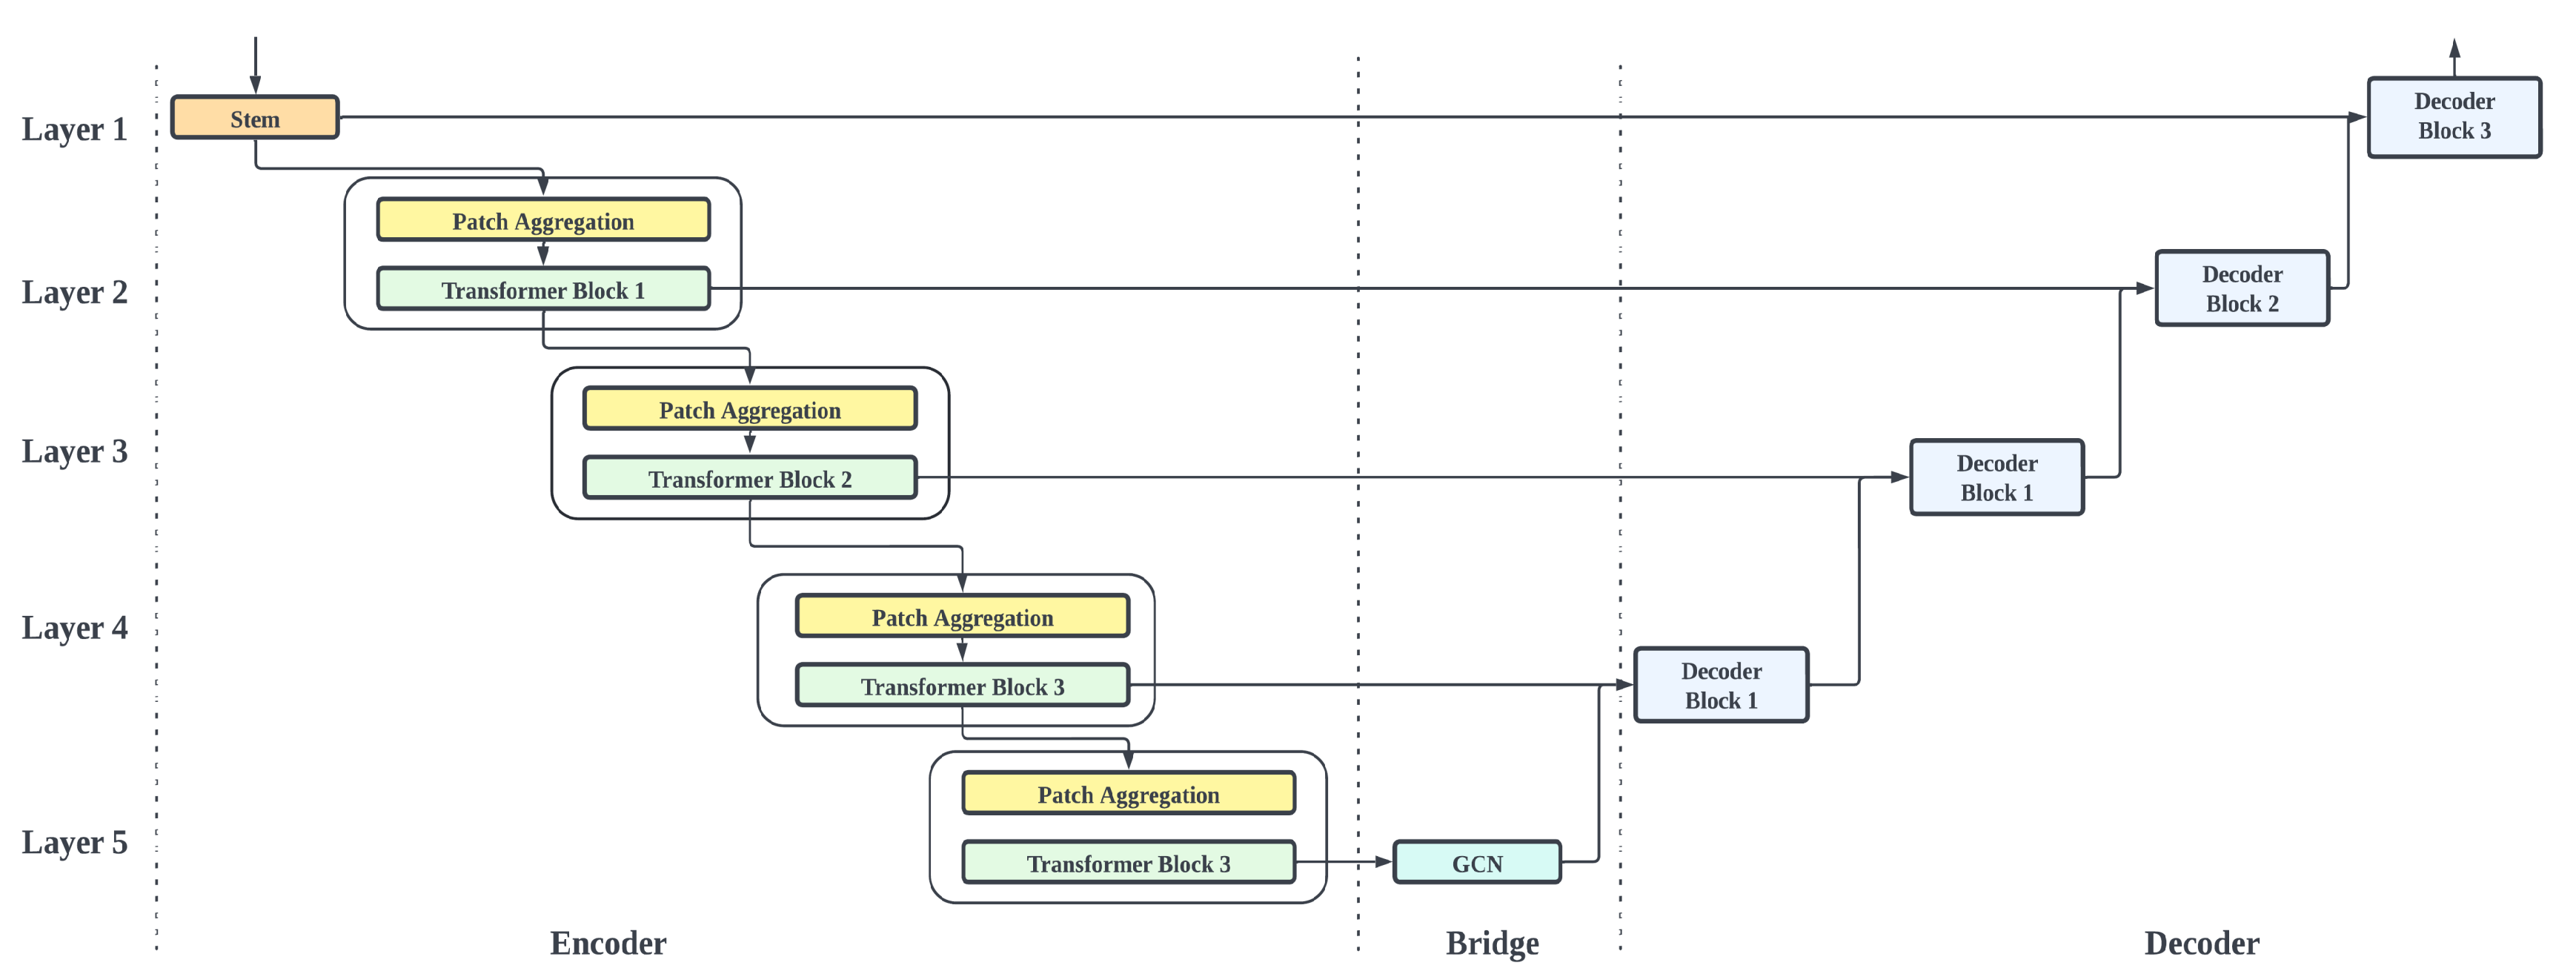

As depicted in Fig. 3, the proposed UGformer consists of an encoder, a U-Net decoder [22], and a bridge. Specifically, the encoder is constructed by ETB, while deconvolutions are used to build the decoder. They are connected by the bridge with GCN.

Each encoding layer (seen in Fig. 3) is constructed by a Patch Aggregation Block. Be noted that the transformer operation is not designed to downsample the feature dimension. Instead, it is constructed by the Patch Aggregation Block, including a kernel and a stride operation with two steps to fulfill the hierarchy structure.

Besides, each layer also contains an ETB (seen in Fig. 4) to enable the UGformer to obtain both long-range dependencies and local context.